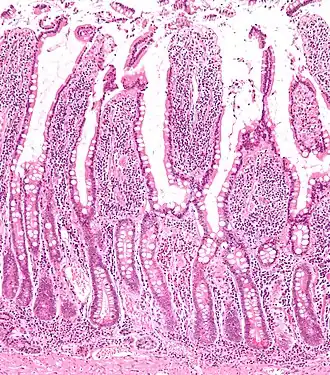

Microanatomy

The three sections of the small intestine look similar to each other at a microscopic level, but there are some important differences. The parts of the intestine are as follows:

| Layer | Duodenum | Jejunum | Ileum |

|---|---|---|---|

| Serosa | 1st part serosa, 2nd–4th adventitia | Normal | Normal |

| Muscularis externa | Longitudinal and circular layers, with Auerbach's (myenteric) plexus in between | Same as duodenum | Same as duodenum |

| Submucosa | Brunner's glands and Meissner's (submucosal) plexus | No BG | No BG |

| Mucosa: muscularis mucosae | Normal | Normal | Normal |

| Mucosa: lamina propria | No PP | No PP | Peyer's patches |

| Mucosa: intestinal epithelium | Simple columnar. Contains goblet cells, Paneth cells | Similar to duodenum, but the intestinal villus is long | Similar to duodenum, but the intestinal villus is short |

Digested food is now able to pass into the blood vessels in the wall of the intestine through either diffusion or active transport. The small intestine is the site where most of the nutrients from ingested food are absorbed. The inner wall, or mucosa, of the small intestine, is lined with intestinal epithelium, a simple columnar epithelium. Structurally, the mucosa is covered in wrinkles or flaps called circular folds, which are considered permanent features in the mucosa. They are distinct from rugae which are considered non-permanent or temporary allowing for distention and contraction. From the circular folds project microscopic finger-like pieces of tissue called villi (Latin for "shaggy hair"). The individual epithelial cells also have finger-like projections known as microvilli. The functions of the circular folds, the villi, and the microvilli are to increase the amount of surface area available for the absorption of nutrients, and to limit the loss of said nutrients to intestinal fauna.

Each villus has a network of capillaries and fine lymphatic vessels called lacteals close to its surface. The epithelial cells of the villi transport nutrients from the lumen of the intestine into these capillaries (amino acids and carbohydrates) and lacteals (lipids). The absorbed substances are transported via the blood vessels to different organs of the body where they are used to build complex substances such as the proteins required by our body. The material that remains undigested and unabsorbed passes into the large intestine.